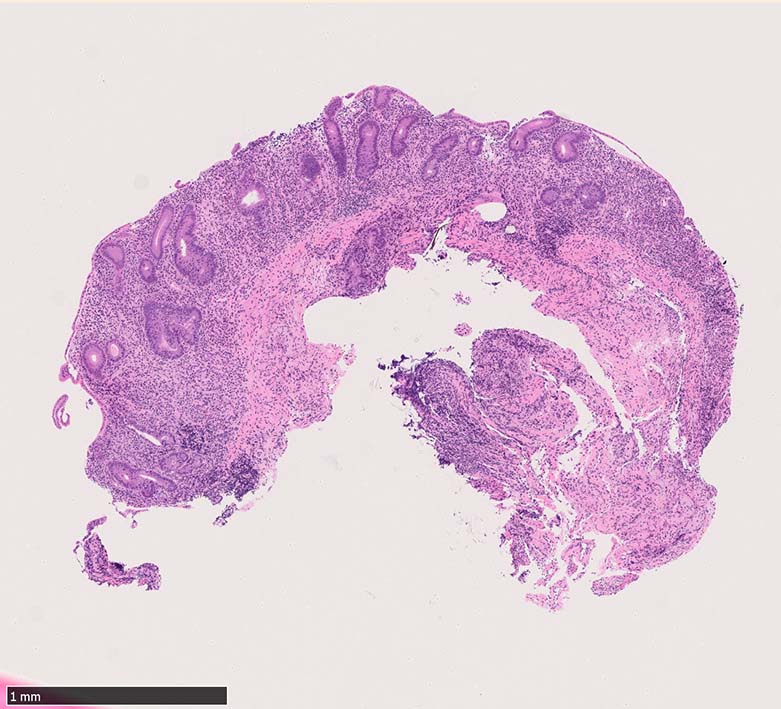

Case presentation

びらんを示す結腸粘膜. 陰窩はdeletion, 萎縮, distortionを呈する. 粘膜固有層には密な慢性炎症がみられ, 好酸球浸潤も多い.粘膜筋板へも炎症細胞浸潤が及ぶ.

UCのような, crypt abscess, cryptitisが認められる. 特徴的な所見として, apoptosis bodiesの増加が見られる.